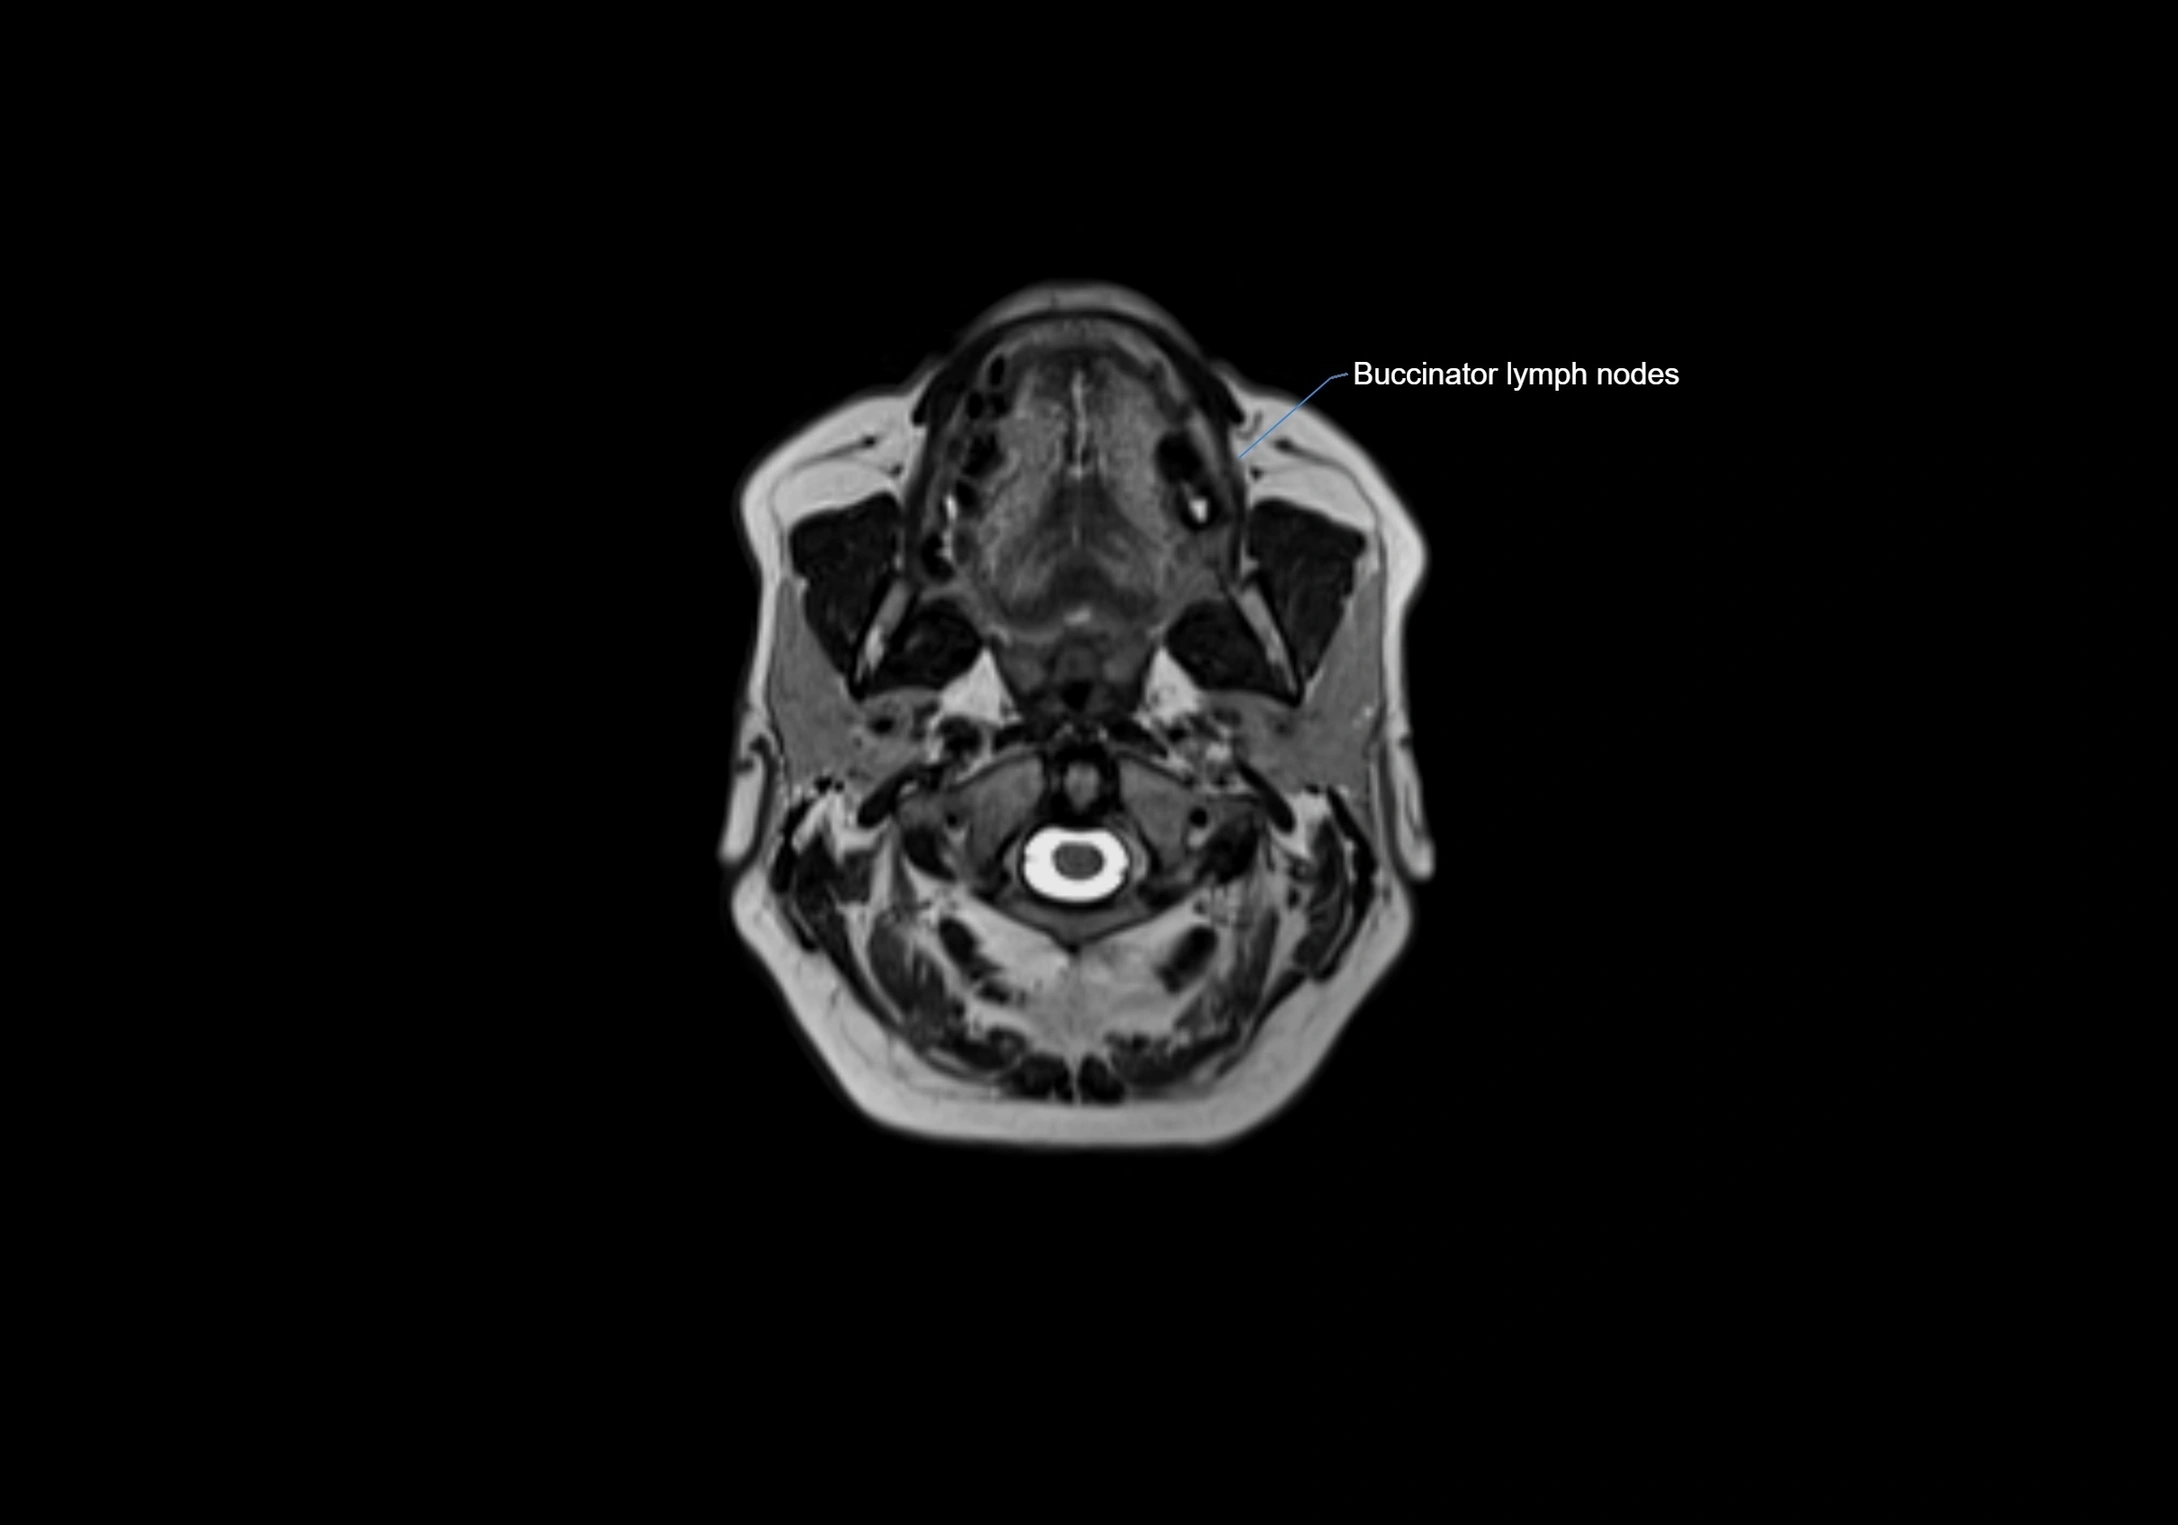

MRI Appearance

T1-weighted images:

• Normal accessory nodes appear as small, oval hypointense to intermediate signal structures within subcutaneous fat

• Surrounded by hyperintense fat, enhancing contrast for visualization

• Pathological nodes may appear enlarged or rounded, sometimes with cortical thickening

MRI images

image